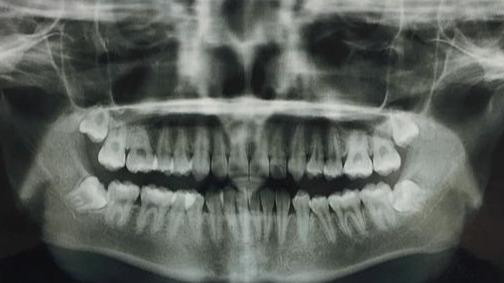

这种情况下,尽早拔掉阻生智齿就是免除后顾之忧最好的选择。甚至我们在条件允许的情况下趁早下手,可以提前拔除智齿的牙胚,不让它有萌出和干扰其他牙齿的机会。现在检查智齿都会拍X全景片,片里可以清楚地看到有没有智齿牙胚,如果没有太大风险的(比如牙胚位于下颌神经管内),我们都可以在智齿萌出之前,选择合适的时机进行开窗拔除牙胚,不让它有作乱的机会。